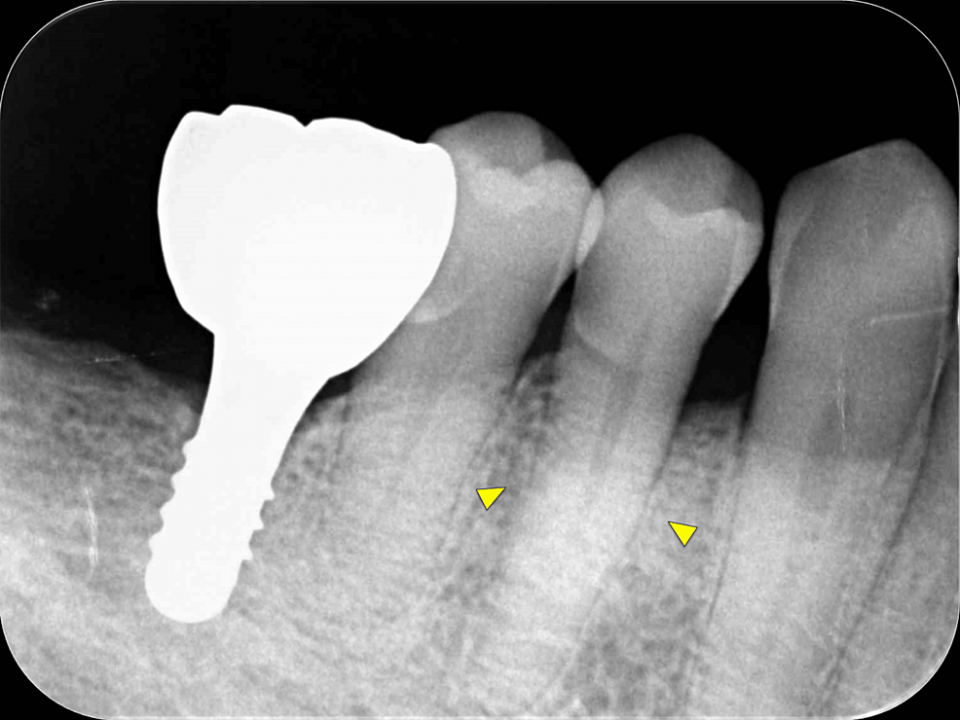

First, initial treatment including oral hygiene instruction was provided, followed by scaling and root planing. Teeth #16, #27, #37, and #46 were extracted, as they were considered too difficult to preserve. After reevaluation, a dental implant was provided for tooth #46. The patient was enrolled in supportive periodontal therapy after it was confirmed that the initial course of periodontal treatment had stabilized conditions. Subsequently, an acute periodontal abscess was observed in #44, however, requiring the start of anti-inflammatory treatment including periodontal pocket curettage under local anesthesia and oral antibiotics. Nevertheless, no improvement was found in the 6-mm buccal pocket of #44, so periodontal tissue regeneration therapy was planned. Before starting such treatment, in addition to intraoral radiography, cone-beam computed tomography (CBCT) was also performed using the 3DX Multi Image Micro CT (J MORITA Co., Ltd., Kyoto, Japan) (Figures 1, 2). The scan parameters were as follows: 90-kV tube voltage; 7-mA tube current; field of view, 60 mm x 60 mm; and slice thickness, 0.125 mm. The CBCT images revealed an intrabony, two-walled, defect around #44 that was slightly less radiolucent on the intraoral radiographic image. It was localized on the buccal side from the proximal to the distal aspect. A relatively large mandibular torus interior was also observed on the lingual side of #44 and #43.

Intraoral radiography and CBCT scanning were performed 14 months postoperatively (Figures 4, 5). The results were displayed on a personal computer monitor screen, and the morphology of the bone at the surgical site and its internal structure was observed in 3D, by which the regrowth of bone-like structures at the site of the intrabony defect was confirmed. At two years postoperatively, no subjective symptoms such as pain or objective signs such as tooth movement or gingival recession were observed. No other notable findings or abnormalities were observed, and the postoperative course was judged to be good.